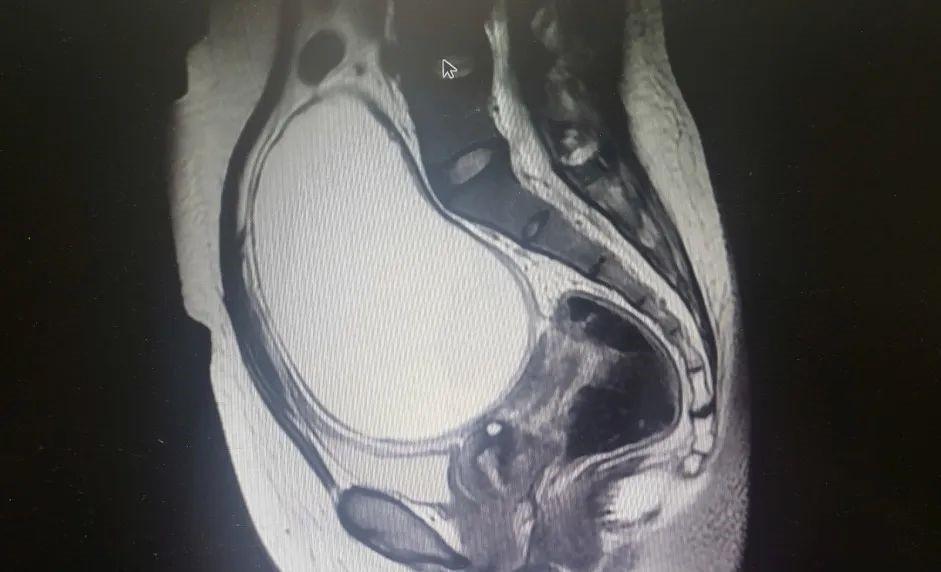

37岁的张女士全身乏力,恶心呕吐一周有余,自行服感冒药、抗生素无效后,前来长安区医院妇产科二病区就诊。经相关检查,显示患者子宫前方见一大小约11.5X9.0X12cm囊性包块,临近子宫、膀胱、肠道均受压,盆腔内积液。介于患者反复高热,输注消炎药物不能改善,血常规提示血象较高,疼痛症状无明显缓解,考虑盆腔脓肿,严重者可能出现脓毒血症,危及患者生命安全,需立即手术治疗。

经过周密的术前准备,手术如期进行。术中可见患者盆腔内有一20X30cm巨大囊性包块,占据整个盆腔,部分突出于腹腔。包块周围与肠管,膀胱,两侧盆腹壁致密粘连,盆腔内黏连严重。穿刺针穿刺抽吸囊液后,见囊液呈黄绿色脓性,考虑为盆腔脓肿,给予行盆腔脓肿引流术,吸出脓液200m1给予脓肿减压后,沿穿刺部位切开一小口,吸引器吸出脓液约1500mL,随行病灶切除术。本例手术难度大,但在多学科协作下,手术得以顺利完成。目前张女士已康复出院。